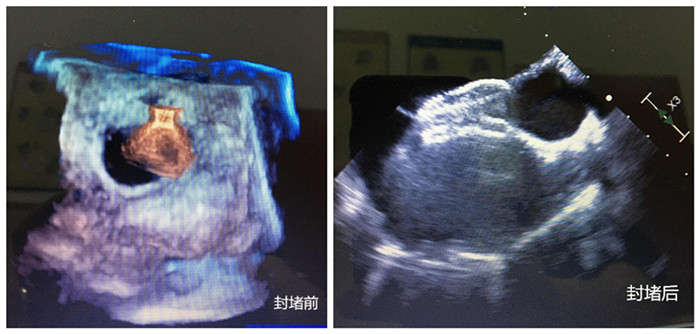

無影燈下,主刀醫(yī)生周珉在小強的右腋下切了一個長度為4cm左右的切口,隨后,在經(jīng)食管探頭的引導下,封堵器順利通過心臟缺損部位,完成釋放和固定,牢牢地堵住缺口,“心臟正常的血液循環(huán)途徑恢復!”僅30分鐘,小強的心臟修補成功。

封堵前、封堵后兩張圖

守在手術室外的家人表示難以置信。三天后,小強便順利出院。